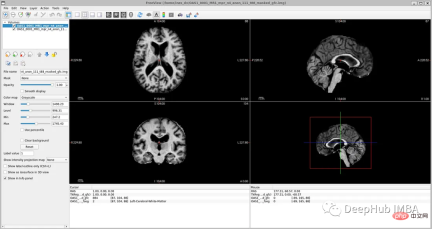

<code>image_filename = root_dir + '/Oasis_Data_Processed/OAS1_0001_MR1_mpr_n4_anon_111_t88_masked_gfc.nii' label_filename = root_dir + '/Oasis_Labels_Processed/OAS1_0001_MR1_mpr_n4_anon_111_t88_masked_gfc_fseg.nii' subject = torchio.Subject(image=torchio.ScalarImage(image_filename), label=torchio.LabelMap(label_filename)) subject.plot()</code>

因为模型需要的是二维切片,所以将每个切片保存在不同的文件夹中,如下图所示。这两个代码单元将训练集的每个MRI体积的切片保存为“.png”格式。

最后我们要看看模型是如何推广到未知数据的这个模型预测的几乎所有东西都是左脑白质,一些像素是左脑皮层。尽管它的预测似乎是正确的,但仍有很大的改进空间,因为我们的模型太小了,可以选择更深的模型获得更好的效果。